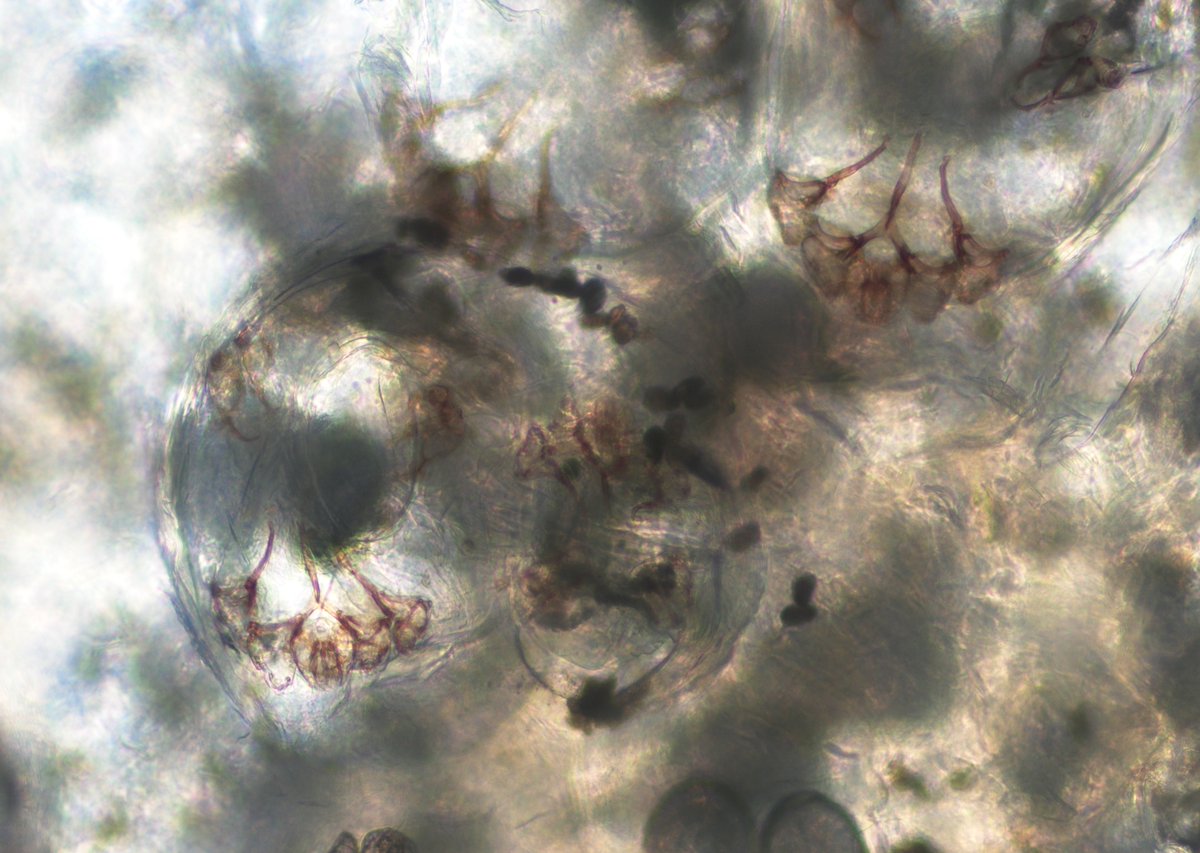

@ParasiteGal

Bobbi Pritt, MD

3 days

#Parasite case 801 is up โ€“ found in skin scrapings. What is your diagnosis, and what forms are you seeing? https://t.co/kGbR7cJRwH Answer later this week! #mayopath #pathology #PathBugs